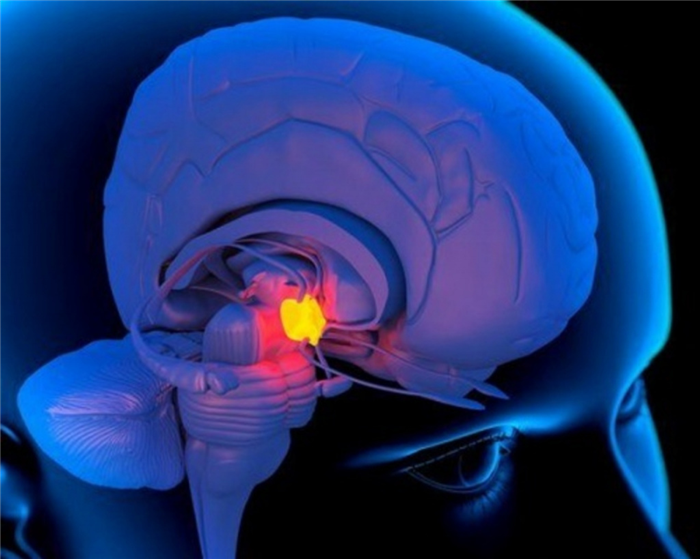

Рисунок 1. Расположение гипофиза в головном мозге. Источник: Patrick J. Lynch, medical illustrator / Wikipedia (CC BY-SA 3.0)

Орган располагается под головным мозгом, а если быть точным — под нижней его частью — гипоталамусом. Последний при этом связан с гипофизом посредством ножки, или гипофизарного стебля. Над гипофизом натянута мембрана, которая отделяет его от головного мозга. Таким образом, орган с одной стороны изолирован от образований головного мозга, а с другой стороны неразрывно связан с ними посредством ножки.

Месторасположение железы

Орган локализуется в нижнем мозговом отделе, относится к его отросткам. Гипофиз базируется в центре черепной коробки, выше него находится гипоталамус. Придаток размещен в углублении клиновидной кости, в большинстве случаев он полностью его заполняет, иногда – только половину объема. При гипертрофических изменениях орган может выходить за пределы костного кармана.